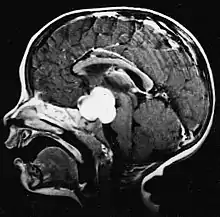

Pilocytic astrocytoma (and its variant pilomyxoid astrocytoma) is a brain tumor that occurs most commonly in children and young adults (in the first 20 years of life). They usually arise in the cerebellum, near the brainstem, in the hypothalamic region, or the optic chiasm, but they may occur in any area where astrocytes are present, including the cerebral hemispheres and the spinal cord. These tumors are usually slow growing and benign, corresponding to WHO malignancy grade 1.[1]

Usually – depending on the interview of the patient and after a clinical exam which includes a neurological exam and an ophthalmological exam – a CT scan and/or an MRI scan will be performed to confirm the presence of a tumor. They are usually easily distinguishable from normal brain structures using these imaging techniques. A special dye may be injected into a vein before these scans to provide contrast and make tumors easier to identify. Pilocytic astrocytomas are typically clearly visible on such scans, but it is often difficult to say based on imaging alone what type of tumor is present.